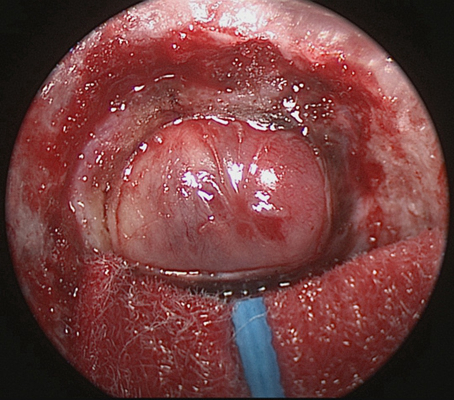

鼻竇炎圖片